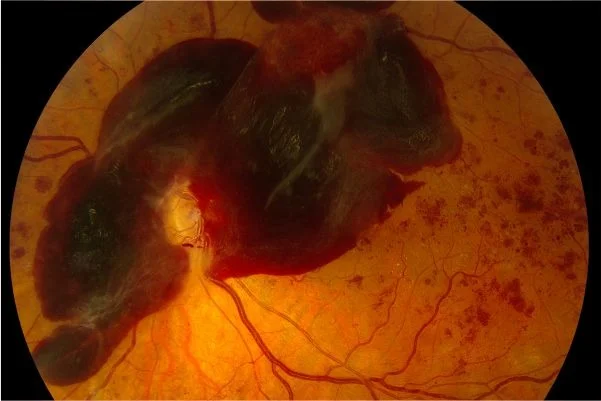

استئصال السائل الزجاجي وحقن السيليكون لعلاج النزيف والتليف السكري

لو لم يتم علاج الارتشاح السكري وقصور الدورة الدموية السكري في مرحلة مناسبة بالأرجون ليزر يحدث نزيف على سطح الشبكية ثم بالسائل الزجاجي في تجويف العين، لو حدث هذا النزيف غالبا ما يحتاج المريض لعملية استئصال للسائل الزجاجي الذي يحتوي النزيف، وحقن مادة السليكون لمنع مزيد من النزيف وملء تجويف العين، وذلك بشكل مؤقت ثم إزالته في تدخل آخر في خلال ٣-٦ شهور.